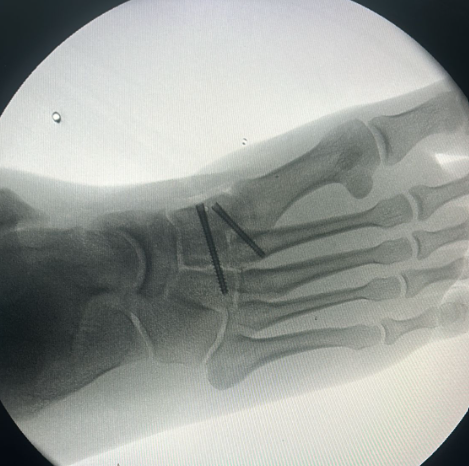

Ayak cerrahisi görseli Ayak cerrahisi görseli 2

• Açık cerrahi: Halluks valgus, aşil tendonu onarımı veya kırık cerrahisi